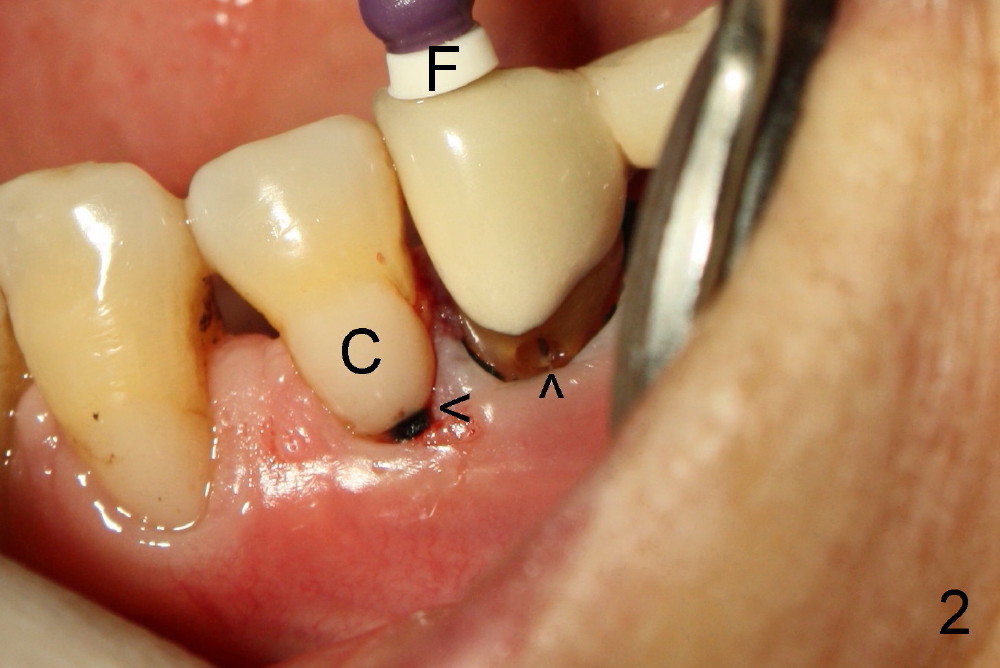

我们先修复颈部缺损(图三黑箭头),然后完成根管治疗,最后用树脂封闭牙合面开口(白箭头),图四显示根管治疗完毕;第一(P1)第二(P2)双尖牙牙根很接近,做植牙有难度。